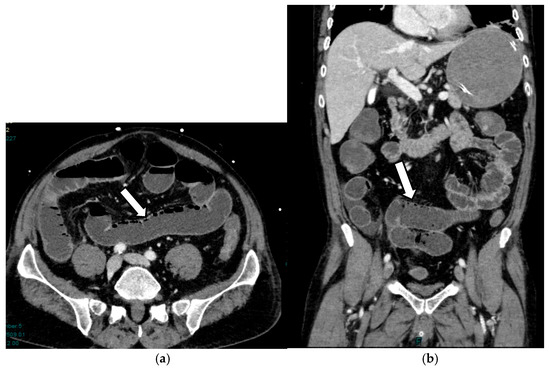

Acute mesenteric ischemia (AMI) is a clinical condition caused by vascular insufficiency, resulting in intestinal damage. Is often underestimated, if not driven by clinical suspicion, due to the non-specific clinical symptoms (usually represented by acute abdominal pain) and the absence of reliable markers, which results in a poor prognosis and high mortality. We can identify three main forms of AMI: arterial, venous, and non-occlusive. Arterial AMI is the most frequent form, caused by occlusion of the superior mesenteric artery or one of its branches. Venous AMI is the least frequent, caused by thrombosis of the superior mesenteric vein or its branches. Non-occlusive AMI is due to a state of hypovolemia, which is frequent in patients who have undergone surgery. Given the difficulty of diagnosis based on the clinic alone, the radiologist plays a central role in identifying radiological signs of intestinal ischemia and in avoiding misdiagnosis. The radiologist’s role is mainly to identify factors predictive of necrosis, which allow us to stratify patients and direct them towards the proper management. The aim of this review is to provide indications for an adequate CT protocol, including an unenhanced phase, an arterial phase, and a venous phase, as well as to underline the features to investigate in the different forms of AMI, in order to increase the diagnostic capacity in this challenging disease. Full article

Show Figures

Figure 1